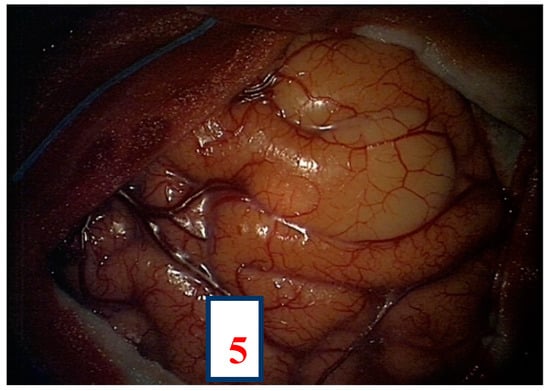

A 32-year-old left-handed female patient was referred to our department with an MR scan showing a right fronto-opercular diffuse low-grade glioma and performed as a diagnostic work-up for headache (Figure 1). Left-handedness was confirmed with Edinburgh’s inventory. She had no preoperative language disorders.

Figure 3. Intra-operative picture showing Broca’s area (number 5) identified by direct electrical stimulation.